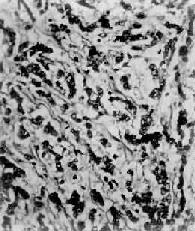

胃硬癌

图10-18 胃硬癌

粘膜下层显著增生的纤维组织内有癌细胞浸润,癌细胞排成窄条索状